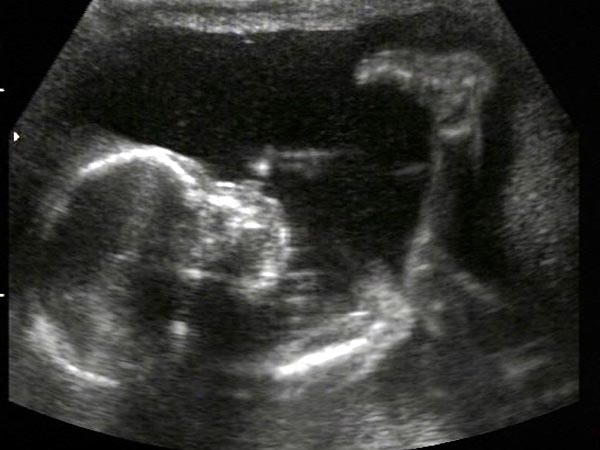

На ультразвуковом исследовании врач анализирует расположение и размеры головки малыша. Скорее всего, она располагается в нижней части матки. Жировая прослойка под кожей продолжает увеличиваться.